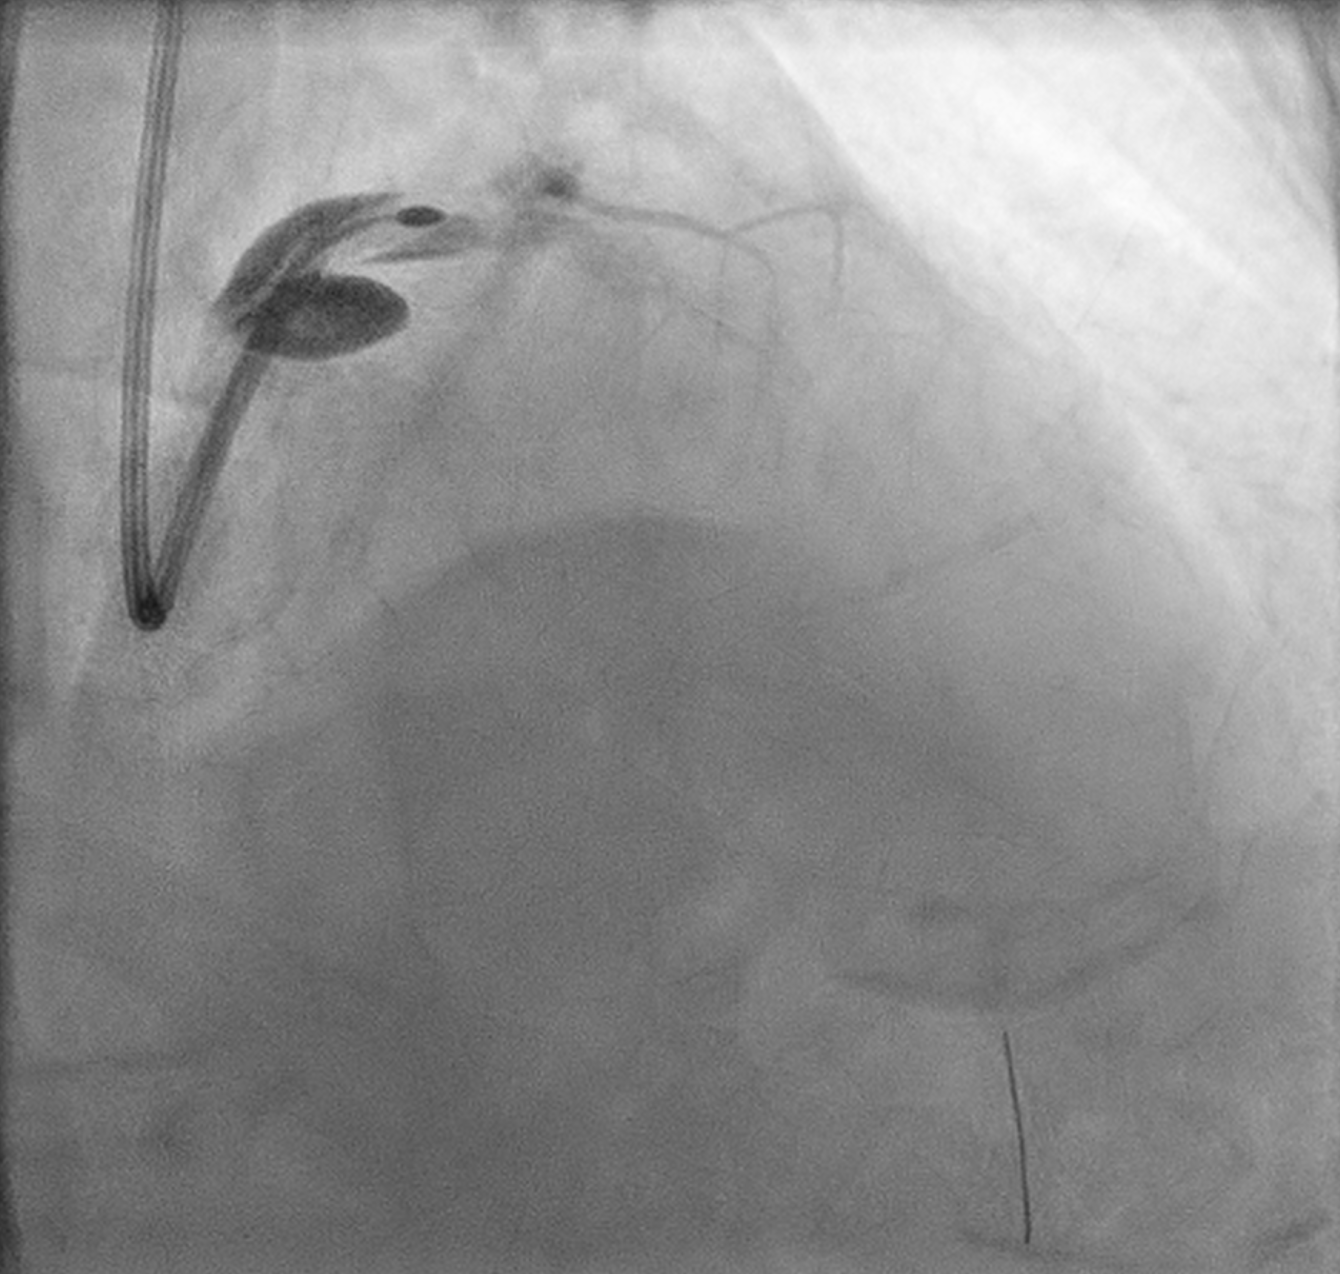

PCI was initiated with Full Dose Heparin. LAD wired with Runthrough NS Floppy; predilatation with 2.0 ¡¿ 15 mm SC balloon. IVUS failed to cross proximal LAD, showing nodular calcium. Rotational atherectomy was performed using Rotapro 1.75 mm burr (180,000 rpm, four runs) followed by one polishing run at 150,000 rpm. Chest pain and ST elevation occurred shortly after rotablation due to Type F dissection in distal LM (TIMI 0 LAD). Bailout stenting with Promus Premier 3.5 ¡¿ 38 mm from LM–LAD was performed using jailed-balloon technique, followed by post-dilatation and IVUS optimization.